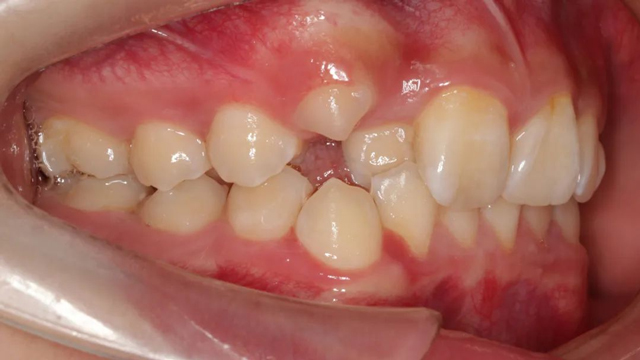

2021年8月(矯正前口內(nèi)照)

這位小患者的口腔問(wèn)題包括:牙列不齊,個(gè)別門牙反頜,左上尖牙完全埋伏阻生,另外,CBCT顯示右上門牙牙根腭側(cè)內(nèi)還有一顆多生牙。

簡(jiǎn)單地說(shuō),牙齒不整齊只是小問(wèn)題,他更大的問(wèn)題是:在不該長(zhǎng)牙的地方多長(zhǎng)了一顆牙,而乳尖牙滯留,早該替換出來(lái)的尖牙長(zhǎng)不出來(lái),這兩顆牙的問(wèn)題如果不及時(shí)干預(yù)治療,會(huì)帶來(lái)很多長(zhǎng)期的口腔問(wèn)題。